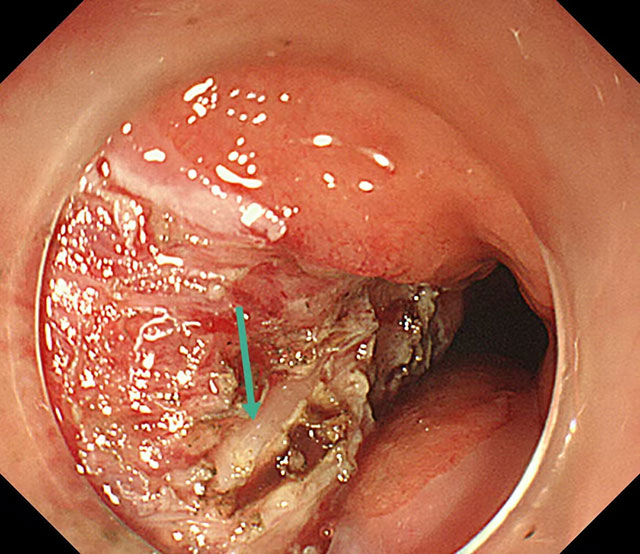

暴露出固有肌层,在肌层内寻找到异物

拔出异物的过程

手术台上,刘蔚先小心翼翼切开脓肿处的食管黏膜,大量黄色脓液瞬间涌出,先为食管“排脓减压”;随后逐层探查,黏膜下层翻找无果,便屏住呼吸,在毫厘之间轻轻切开固有肌层,目光紧紧锁定视野,在与肌肉颜色近乎一致的地方,终于发现了那根“藏猫猫”的鱼刺!刘蔚轻夹鱼刺,慢慢提拉,生怕稍一用力刺破食管壁,这根长度1.5厘米的鱼刺,终于被成功取出,与CT报告完全吻合。